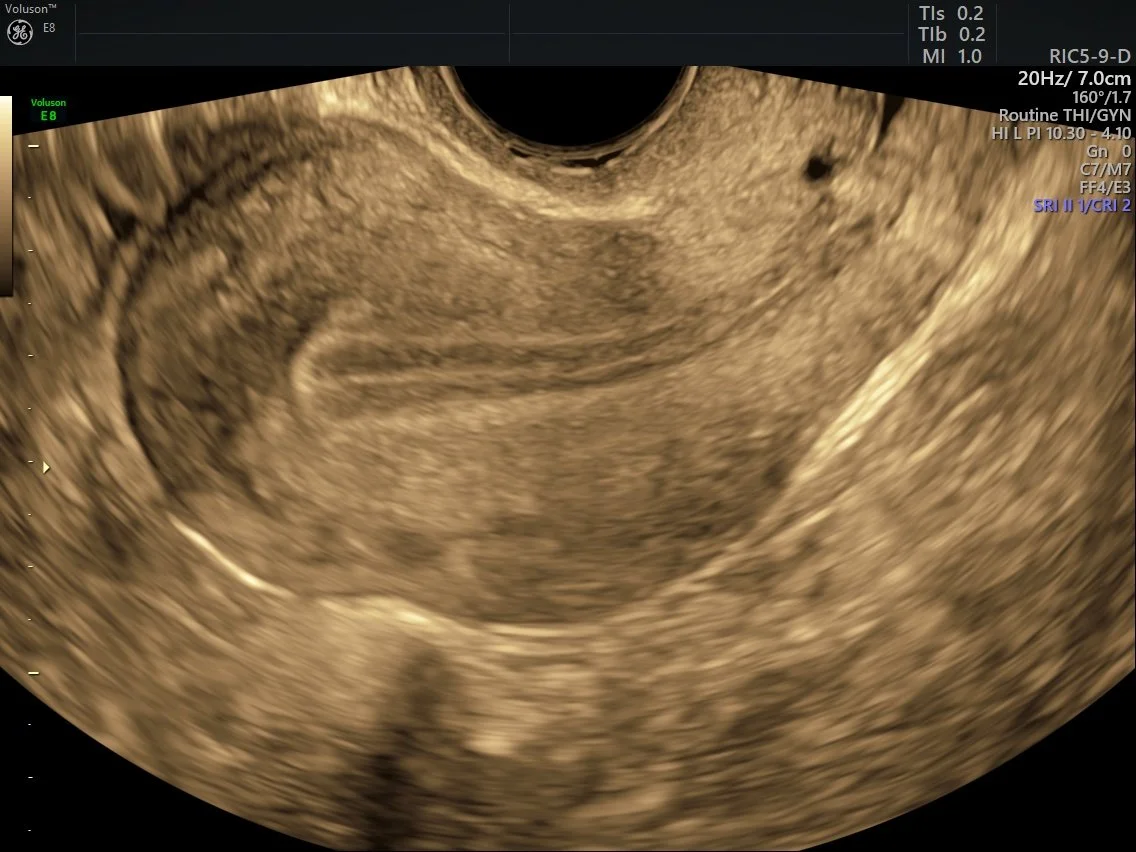

Transvaginal ultrasounds are performed alongside a normal pelvic ultrasound, using a small, sterile probe. The transducer is covered in a disposable protective cover with lubricating gel.

The transducer is slightly thicker then a tampon and its long length provides a handle for the Sonographer to grasp for imaging purposes.

The insertion of the probe is similar to the insertion of a vaginal speculum that most women have experienced during a PAP smear examination.

Only a small portion of the transducer will be gently placed inside the Virginia. Following the insertion, the Sonographer moves the transducer from side to side, up and down to assess the pelvic organs and/or pregnancy. The Sonographer may also need to put pressure on the lower abdomen to move bowel out of the way and to bring the pelvic structures into view for assessment. These manoeuvres allow mobility of the organs to be assessed. It also helps to identify any points of tenderness for closer inspection with the probe.